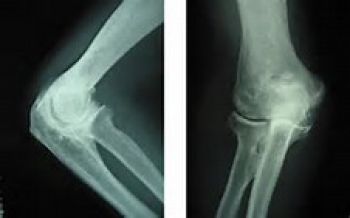

変形性肘関節症の診断

問診(職業の他、運動の経験などの問診)、診察、X線検査などを行います。

X線撮影で骨の変形具合を確認します。

関節リウマチや神経の病気との鑑別が必要になります。